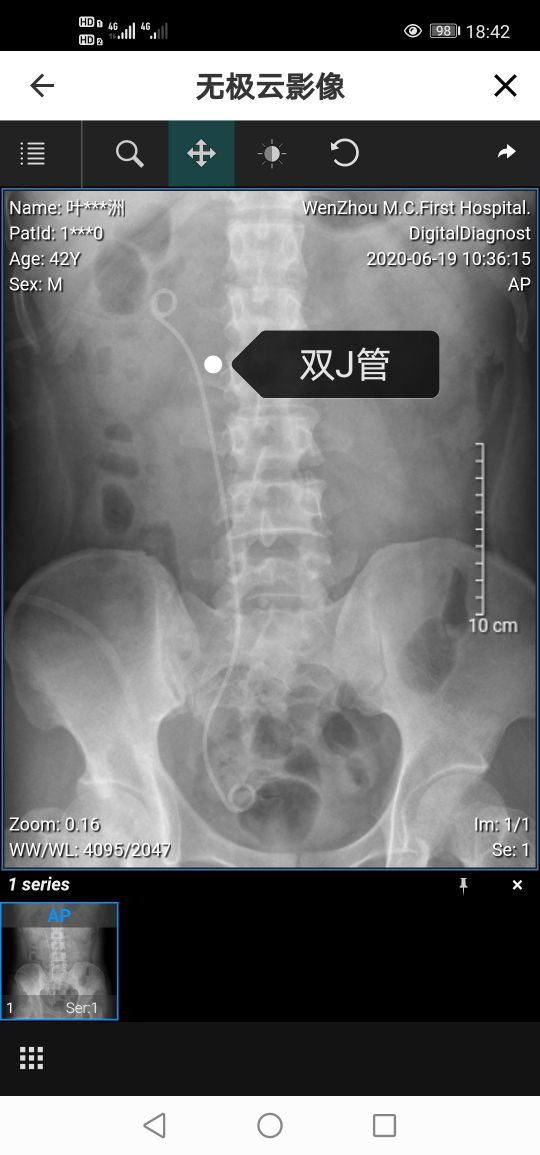

第二天,坐在轮椅上被人推着去拍了片子。从片子里可以清楚的看到一根双J管通过输尿管连着肾脏和膀胱。其作用就是支撑输尿管,防止血液或者残余结石堵塞输尿管,起到了一个疏通的作用。并且,肾部也看不到任何结石的残留,说明手术还是成功的。

然而,在拔完导尿管后上厕所,我又经历了剧烈的疼痛。每次开始还好,但是尿到一半腰部会产生十分剧烈的疼痛,痛的腿都站不住,必须要用手扶着旁边才不至于摔倒。问过医生,原来是小便时由于膀胱的收缩引起尿液回流回肾脏引起的。我们身体本身的输尿管是一个单向的管道,尿液下去后就不会回流,但是这个时候,链接肾脏和膀胱的那根双J管还在体内,暂时丧失了这一单向的功能。而且,这双J管还要继续服役一个多月才能拔除,直到拔除了双J管才算是结束了肾结石手术的最后一个步骤。也就是说,排尿的疼痛还要持续一段时间。当然,我也掌握了一些技巧,比如小便时不会过于用力,而且一旦感觉疼痛来临,就刻意先憋住,等痛感消失了再缓慢继续。虽然麻烦了一点,但是没办法,生病本身就是一个麻烦的事情。